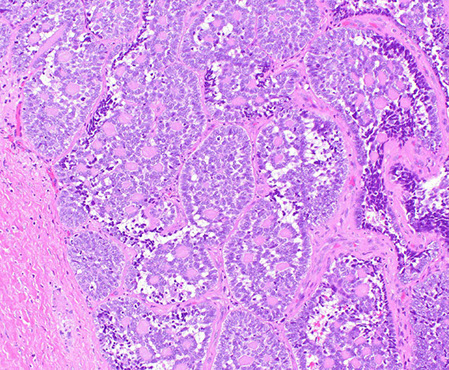

Juvenile polyps

- aka Retention polyp (if solitary lesion?)

Sporadic, usually solitary in kiddos <5 yo. 80% in rectum.

- Not malignant if single; not usually assoc c juvenile polyposis syndrome

- MCC rectal bleeding in children; and may cause intussusception

- MC pediatric polyp (9/10)

- considered hamartomatous, so so in colon they have irregular, dilated glands c edema and granulation tissue in the lamina propria

Micro: Disorganized crypts, dilated glands filled c neutros and mucin c edematous lamina propria

spherical lobulated surface, usually eroded

Classic juvenile polyps. A, These polyps grossly appear rounded, smooth, and unilobular with an erythematous cap of eroded tissue. (A, Courtesy of Thomas C. Smyrk, MD, Mayo Clinic, Rochester, MN.) B, Their cut surface reveals multiple dilated, mucin-filled crypts, leading to the term mucus retention polyp. C, At higher power, the crypts are dilated and branched. Some, like the one at center, contain crypt abscesses, collections of neutrophils, or eosinophils. The surrounding stroma is also expanded and contains numerous mixed inflammatory cells. [2]